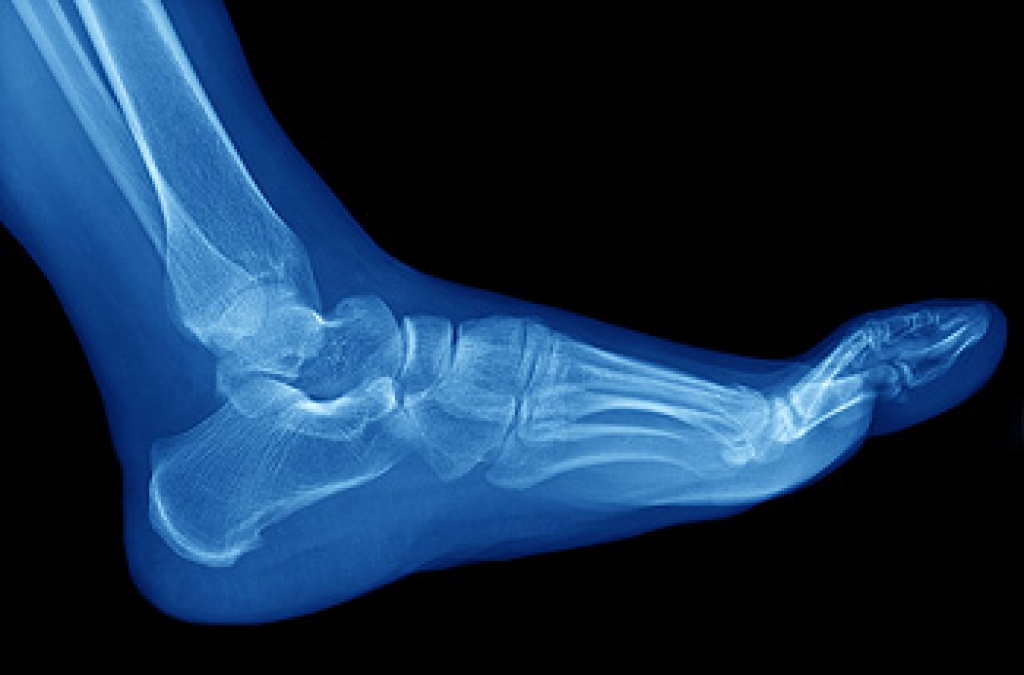

In many cases the cause of toe pain is obvious, but in others, a podiatrist may want to use more advanced methods to determine the problem. These can range from simple visual inspections and sensation tests to X-rays and MRI scans. Prior medical history, family medical history, and any recent physical traumatic events will all be taken into consideration for a proper diagnosis.